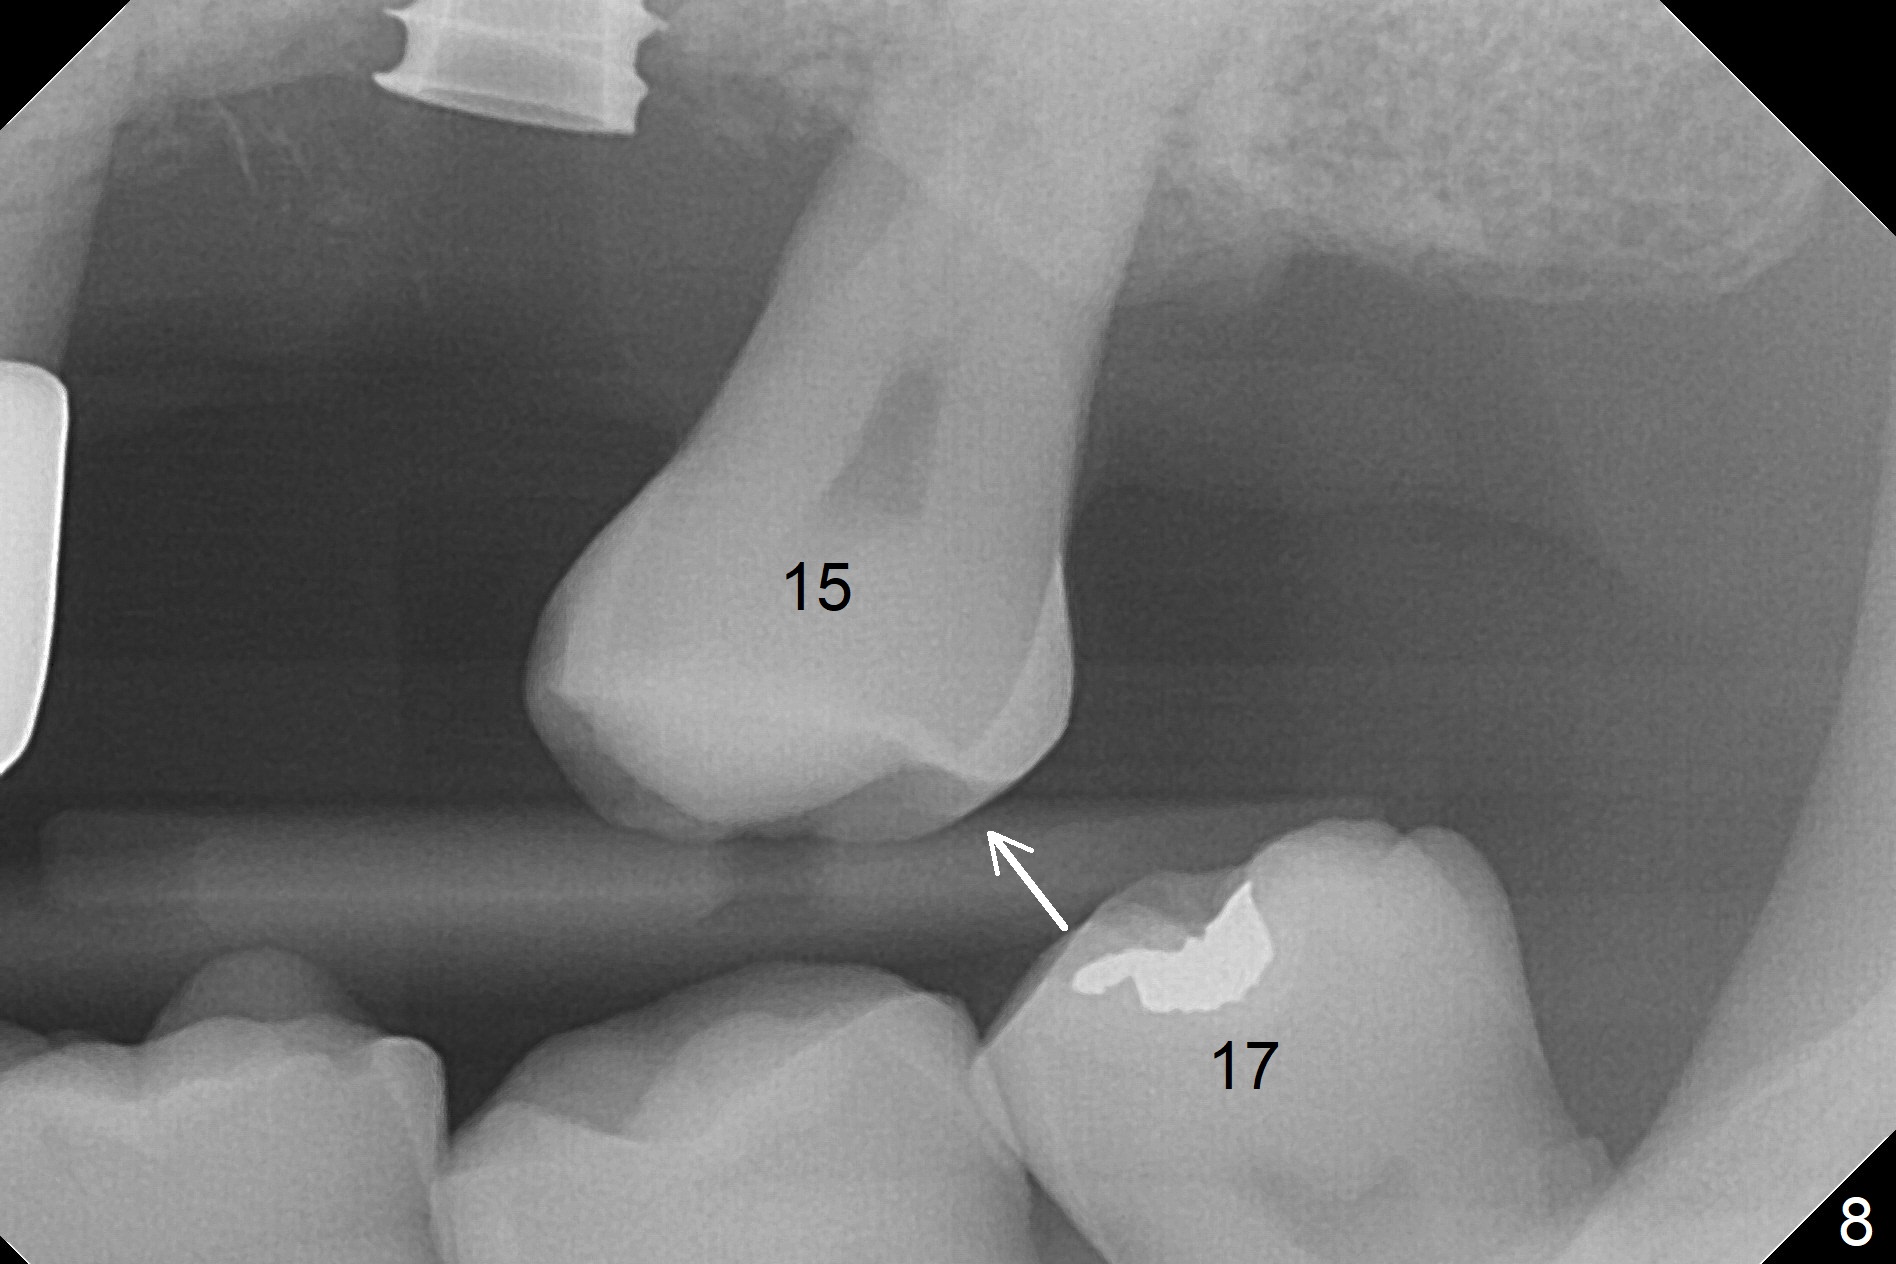

The amount of the bone graft mesial and distal the implant seems to reduce 3 and 4 months postop, respectively (Fig.6,7 arrowheads). When the acrylic is cut off 4 months postop, the bone graft is loose. The gingiva is unhealthy. The abutment and implant are loose. A healing abutment is placed (5x4 mm). The implant is torqued to 35 Ncm 6 months postop with the healing abutment reapplied. The patient will return for follow up nearly 9 months postop. A larger healing abutment will be used if the implant is stable. Two weeks later, use a smaller restorative abutment for easy impression. In fact the implant is unstable with #15 mesial shift due to abnormal occlusion with #17 (Fig.8). Bone density around the implant is low (* in Fig.9 (PA), 10,11 (CT sagittal, coronal sections)). A healing screw is placed for self healing. A 2nd option is to remove the implant (Fig.12), BEB (Fig.13) and place the implant deeper (Fig.14) or larger one (5.5-6.5x13 mm). The 3rd option is to place larger and longer implants (Fig.15 (tapered), 16 (cylindrical)). The implant access has partially closed 14 months postop, but there is a small buccal opening with sanguine exudate. Incision reveals severe bone loss around the implant; the mobile tooth #15 is extracted (Fig.17). After debridement and irrigation with normal saline, Vera Graft (Fig.18 *) and Collagen plug are placed with periodontal dressing.